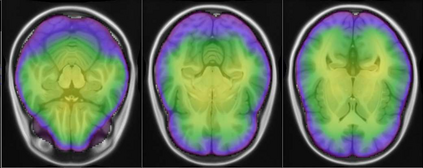

Representational similarity analysis (RSA) is a multivariate technique to investigate cortical representations of objects or constructs. While avoiding ill-posed matrix inversions that plague multivariate approaches in the presence of many outcome variables, it suffers from the confound arising from the non-orthogonality of the design matrix. Here, a partial correlation approach will be explored to adjust for this source of bias by partialling out this confound. A formal analysis will show the dependence of this confound on the temporal correlation model of the sequential observations, motivating a data-driven approach that avoids the problem of misspecification of this model. However, where the autocorrelation locally diverges from the volume average, bias may be difficult to control for exactly (local bias), given the difficulties of estimating the precise form of the confound at each voxel. Application to real data shows the effectiveness of the partial correlation approach, suggesting the impact of local bias to be minor. However, where the control for bias locally fails, possible spurious associations with the similarity matrix of the stimuli may emerge. This limitation may be intrinsic to RSA applied to non-orthogonal designs.